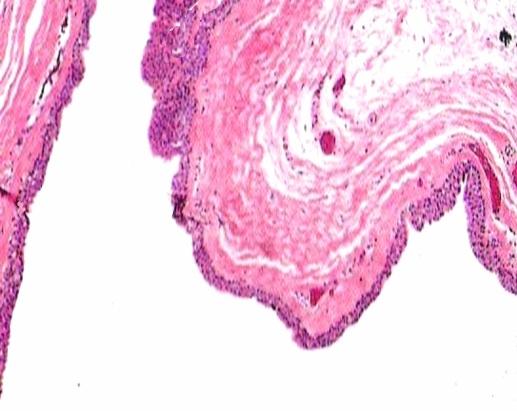

Dermatopathology Case 108 Get link Facebook X Pinterest Email Other Apps November 30, 2011 Image1 Image 2 Image3 Image4 Case 108 A 38 year old male with a nodule on the glans penis. Diagnosis Get link Facebook X Pinterest Email Other Apps